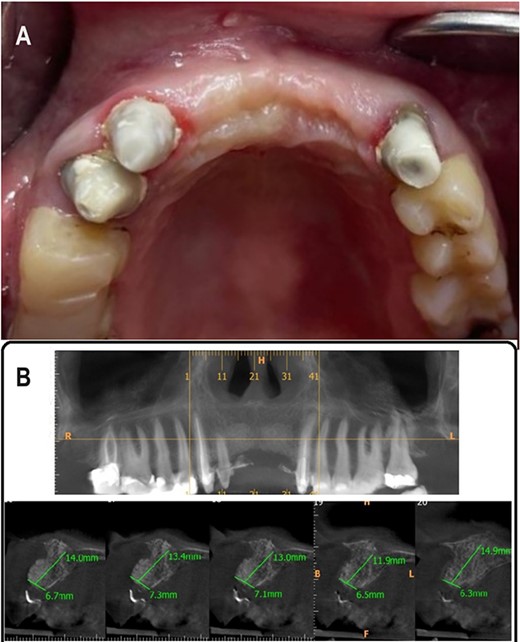

After 5 months, Cone Beam Computed Tomography (CBCT) was done to assess the thickness of the alveolar bone. Alveolar bone thickness was increased 4–5 mm from the baseline, and it ranged from 6.3 to 7.3 mm (Class II according to Tolstunov classification for alveolar ridge defects [13]), which was sufficient to place dental implants (Fig. 4A and B).

(A) 5 months postoperative photograph, (B) 5 months postoperative CBCT.